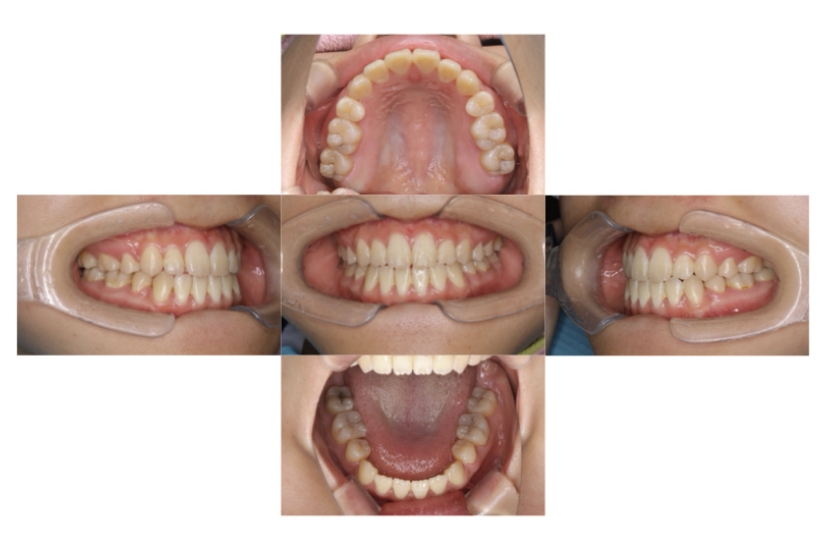

症例1

上顎前突、叢生

抜歯

ブラケット矯正

上下顎叢生、上顎前突(出っ歯、上下の前歯のガタガタ)のケースです。

装置はラビアル(上下表側)で、上顎の小臼歯を2本抜歯を行っています。抜歯したスペースを使って、上の前歯の後方移動と叢生(ガタガタ)と出っ歯の改善を行っています。下は歯と歯の間にIPR(隣接面削合)を行い、スペースを確保し、叢生の改善を行っています。

主訴 前歯のガタガタと出っ歯が気になる。

年齢・性別 47歳 女性

お住まいの地域 神奈川県川崎市

治療方針 抜歯スペースおよびIPRを利用して上前歯の叢生(ガタガタ)の改善

抜歯部位 上顎左右第一小臼歯

使用装置 ラビアル(上下表側)、顎間ゴム

治療期間 2年0か月

治療回数 15回

リテーナー クリアリテーナー

BEFORE

AFTER